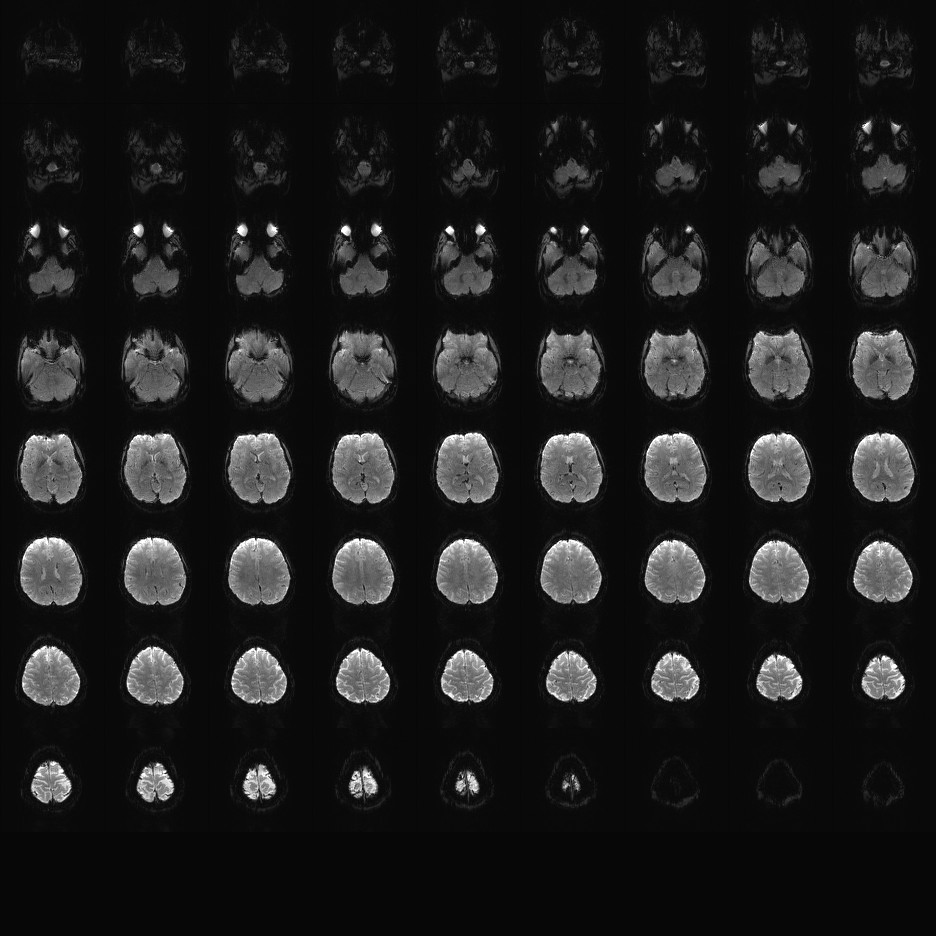

Multi-banded RF pulses can be used to accelerate volume coverage along the slice direction by simultaneously exciting and acquiring multiple slices and subsequently unaliasing them using parallel imaging principles and the spatial information available in multi-channel RF array coils.

This allows for a direct reduction in the volume TR by the number of simultaneously excited slices (i.e., the multiband (MB) factor or the slice acceleration factor).